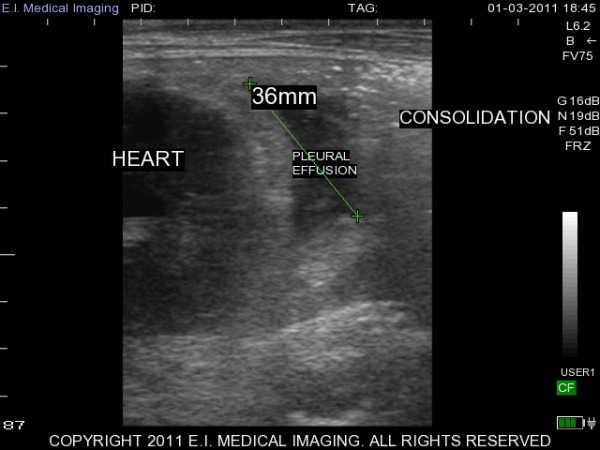

My name is Elizabeth Adams and I am a dairy practitioner in the central valley of California. Recently, I was able to use the IBEX PRO portable ultrasound to look at calf lungs for evidence of damage from calfhood pneumonia. In veterinary school, I scanned all of my patients with respiratory symptoms because it is a fast, non-invasive exam that provides a lot of information quickly. With ultrasound I can see healthy lungs, pleural effusion, atelectasis, consolidation and abscessation.

Ultrasound allows me to look at the surface of the lung; in a healthy lung, this is all we can see as the lung is full of air and doing its job. In a diseased lung, the surface of the lung is abnormal and allows penetration of the ultrasound waves deep into the lung parenchyma. Young calves require only the penetration of a 5-7.5MHz rectal ultrasound probe to see the evidence of damage from previous pneumonia.

Thanks to E.I. Medical Imaging's Research Loaner Program, I was able to scan lungs of calves at approximately three months of age. I am giving each calf a lung score based on the extent of lung damage seen on ultrasound. These heifers will then be followed out to their first freshening and I will see how well they perform in their first lactation. My hypothesis is that calves with extensive lung damage will not perform as well as their herdmates with healthy lungs. I plan to use ultrasound to help producers make more informed decisions when choosing calves to add to their herd.